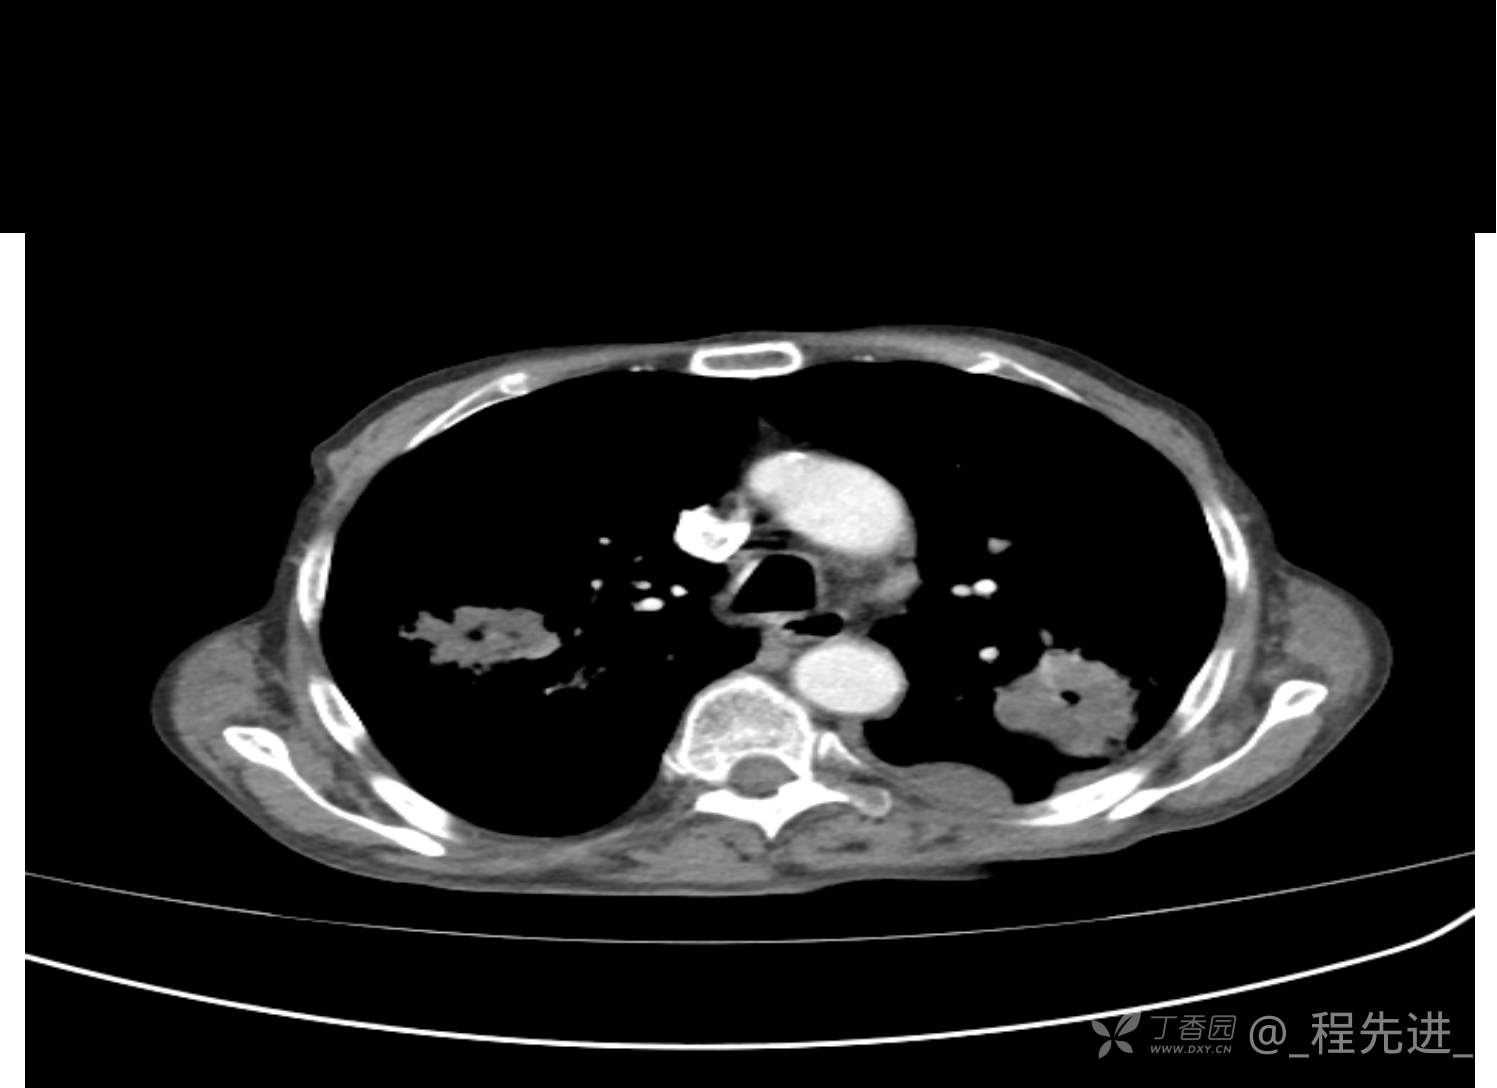

患者性别:男

患者年龄:81岁

简要病史:反复咳嗽、咳痰20余年,加重1周。两肺呼吸音低,可闻及散在干湿啰音。